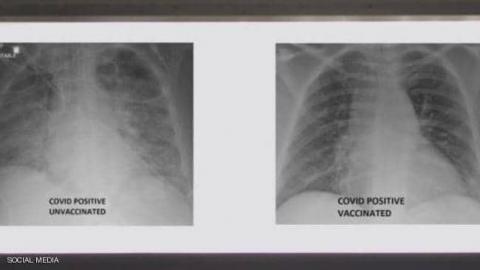

البشام الإخباري/ نشر الطبيب العربي في الولايات المتحدة، غسان كمال، صورة تظهر الفرق بين رئتي شخص جرى تطعيمه ضد فيروس كورونا ورئتي شخص آخر لم يتلق التطعيم، مشيرا إلى أن الاثنين أصيبا بفيروس كورونا.

وأظهرت صور الأشعة السينية أن رئتي الشخص غير الملقح، المصاب بفيروس كورونا كانت بيضاء بصورة شبه كاملة وتعرف بـ"عتامة الرئة"، مما يعني أنها كانت غارقة في الفيروس، في حين أبرز صور رئتي الشخص ببيضاء أقل.

وتعني صورة الأول أيضا نقصا في دخول الهواء إلى رئتيه، فيما تعني لدى الثاني أن الهواء يتدفق بسهولة علاوة على أن رئتيه خاليتين من الوباء.

وأشار إلى أنه نشر الصور من أجل إظهار الفرق الذي يمكن أن يحدثه اللقاح في رئتي الشخص في حال إصابته بالفيروس .